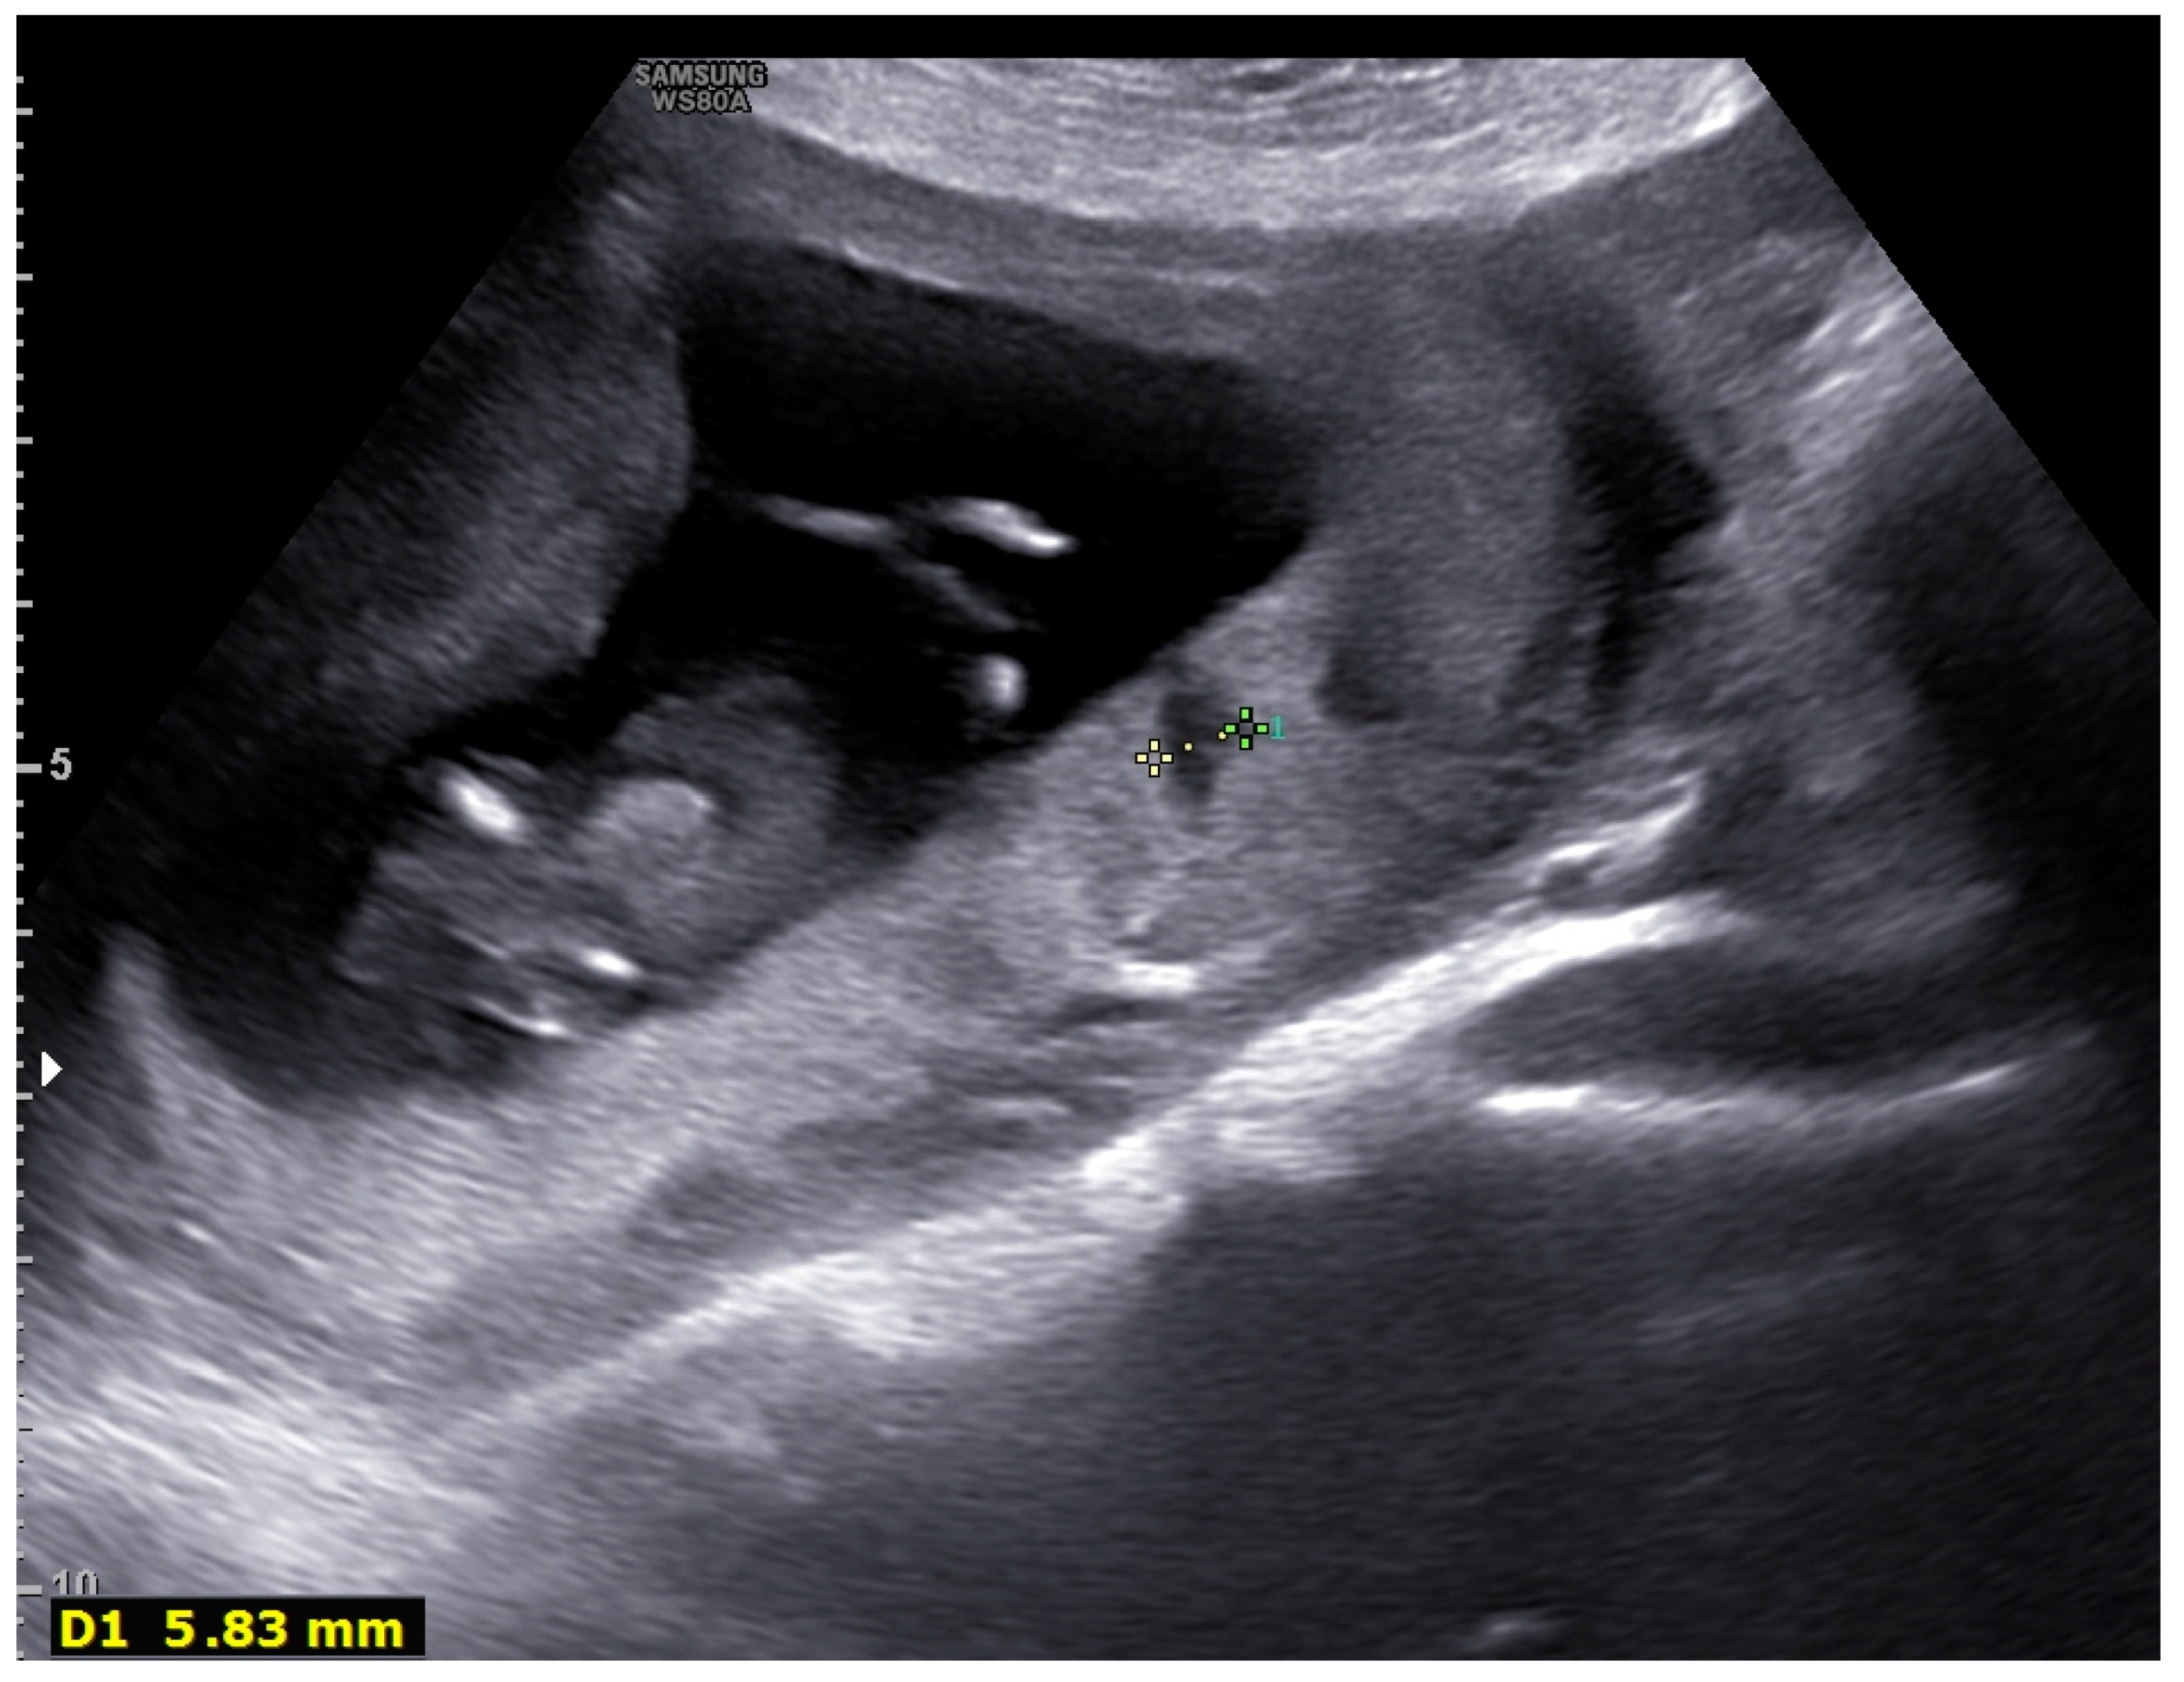

| 1 | Lakes > 30% |

| 1 | Fibrin deposits (thrombosis, calcifications) |

| U/S Findings/Group | Hospital Admission N (%) | Remaining at Home N (%) |

| Normal findings | 0 (0%) | 18 (60%) |

| Lakes > 30% | 7 (70%) | 6 (20%) |

| Subchorionic edema | 6 (60%) | 2 (7%) |

| Fibrin deposits (thrombosis, calcifications) | 6 (60%) | 4 (13%) |